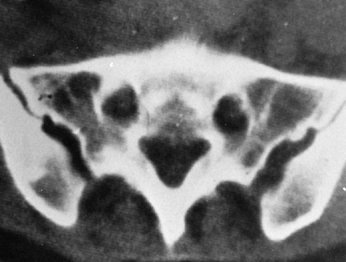

it is relatively subcutaneous, has natural curvatures that are useful

usually there is no significant residual disability. Abbott (1) demonstrated that the posterior third of the ilium is thickest (Fig. 9.4). This is confirmed by computer tomography (CT) scans (Fig. 9.5).

![]() |

Figure 9.5.

This CT scan of the pelvis at the level of the posterosuperior iliac spine illustrates the thickness of the ilium posteriorly and the amount of cancellous bone available. |